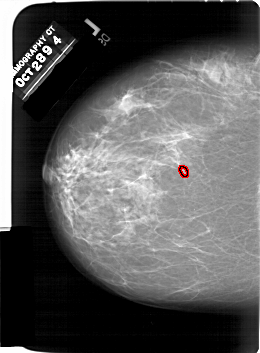

A_1438_1.RIGHT_CC

LEFT_CC LINES 6706 PIXELS_PER_LINE 4936 BITS_PER_PIXEL 12 RESOLUTION 43.5 OVERLAY

FILE: A_1438_1.LEFT_CC.OVERLAY

TOTAL_ABNORMALITIES 1

ABNORMALITY 1

LESION_TYPE CALCIFICATION TYPE PLEOMORPHIC DISTRIBUTION CLUSTERED

ASSESSMENT 4

SUBTLETY 2

PATHOLOGY BENIGN

TOTAL_OUTLINES 1

BOUNDARY